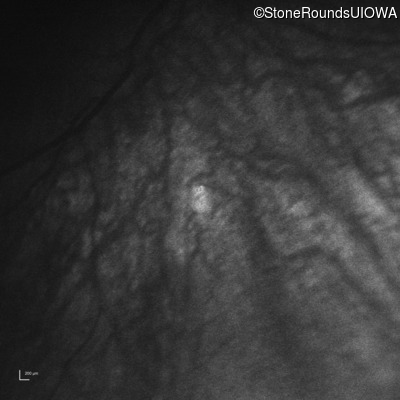

Infrared Fundus Photograph - Right -

No Light Perception

Exemplar

Infrared Fundus Photograph - Left -

Light Perception